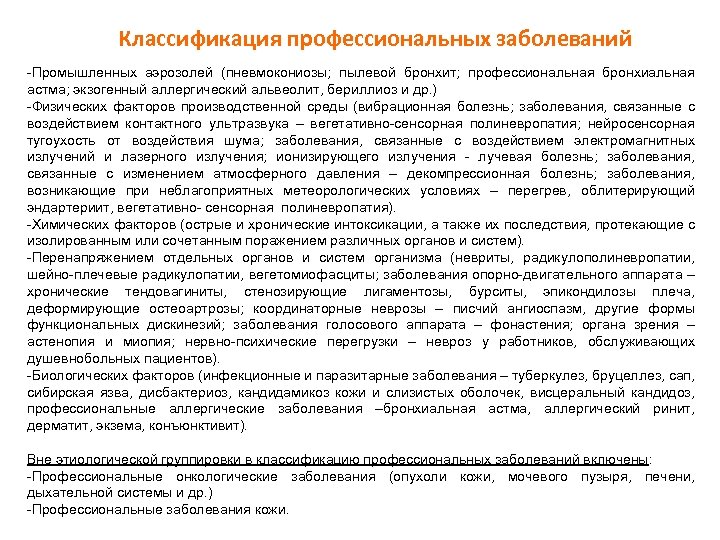

Классификация профессиональных заболеваний Промышленных аэрозолей (пневмокониозы; пылевой бронхит; профессиональная бронхиальная астма; экзогенный аллергический альвеолит, бериллиоз и др. ) Физических факторов производственной среды (вибрационная болезнь; заболевания, связанные с воздействием контактного ультразвука – вегетативно сенсорная полиневропатия; нейросенсорная тугоухость от воздействия шума; заболевания, связанные с воздействием электромагнитных излучений и лазерного излучения; ионизирующего излучения лучевая болезнь; заболевания, связанные с изменением атмосферного давления – декомпрессионная болезнь; заболевания, возникающие при неблагоприятных метеорологических условиях – перегрев, облитерирующий эндартериит, вегетативно сенсорная полиневропатия). Химических факторов (острые и хронические интоксикации, а также их последствия, протекающие с изолированным или сочетанным поражением различных органов и систем). Перенапряжением отдельных органов и систем организма (невриты, радикулополиневропатии, шейно плечевые радикулопатии, вегетомиофасциты; заболевания опорно двигательного аппарата – хронические тендовагиниты, стенозирующие лигаментозы, бурситы, эпикондилозы плеча, деформирующие остеоартрозы; координаторные неврозы – писчий ангиоспазм, другие формы функциональных дискинезий; заболевания голосового аппарата – фонастения; органа зрения – астенопия и миопия; нервно психические перегрузки – невроз у работников, обслуживающих душевнобольных пациентов). Биологических факторов (инфекционные и паразитарные заболевания – туберкулез, бруцеллез, сап, сибирская язва, дисбактериоз, кандидамикоз кожи и слизистых оболочек, висцеральный кандидоз, профессиональные аллергические заболевания –бронхиальная астма, аллергический ринит, дерматит, экзема, конъюнктивит). Вне этиологической группировки в классификацию профессиональных заболеваний включены: Профессиональные онкологические заболевания (опухоли кожи, мочевого пузыря, печени, дыхательной системы и др. ) Профессиональные заболевания кожи.

Классификация профессиональных заболеваний Промышленных аэрозолей (пневмокониозы; пылевой бронхит; профессиональная бронхиальная астма; экзогенный аллергический альвеолит, бериллиоз и др. ) Физических факторов производственной среды (вибрационная болезнь; заболевания, связанные с воздействием контактного ультразвука – вегетативно сенсорная полиневропатия; нейросенсорная тугоухость от воздействия шума; заболевания, связанные с воздействием электромагнитных излучений и лазерного излучения; ионизирующего излучения лучевая болезнь; заболевания, связанные с изменением атмосферного давления – декомпрессионная болезнь; заболевания, возникающие при неблагоприятных метеорологических условиях – перегрев, облитерирующий эндартериит, вегетативно сенсорная полиневропатия). Химических факторов (острые и хронические интоксикации, а также их последствия, протекающие с изолированным или сочетанным поражением различных органов и систем). Перенапряжением отдельных органов и систем организма (невриты, радикулополиневропатии, шейно плечевые радикулопатии, вегетомиофасциты; заболевания опорно двигательного аппарата – хронические тендовагиниты, стенозирующие лигаментозы, бурситы, эпикондилозы плеча, деформирующие остеоартрозы; координаторные неврозы – писчий ангиоспазм, другие формы функциональных дискинезий; заболевания голосового аппарата – фонастения; органа зрения – астенопия и миопия; нервно психические перегрузки – невроз у работников, обслуживающих душевнобольных пациентов). Биологических факторов (инфекционные и паразитарные заболевания – туберкулез, бруцеллез, сап, сибирская язва, дисбактериоз, кандидамикоз кожи и слизистых оболочек, висцеральный кандидоз, профессиональные аллергические заболевания –бронхиальная астма, аллергический ринит, дерматит, экзема, конъюнктивит). Вне этиологической группировки в классификацию профессиональных заболеваний включены: Профессиональные онкологические заболевания (опухоли кожи, мочевого пузыря, печени, дыхательной системы и др. ) Профессиональные заболевания кожи.